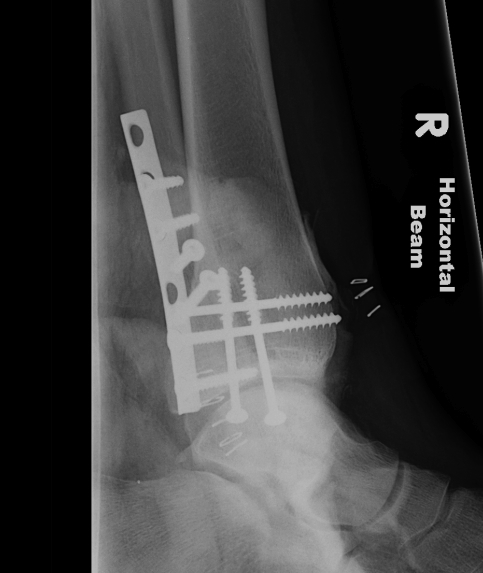

Operative management

Indications

1. Large fragment / ankle joint subluxation

2. Articular incongruency / articular step

3. Syndesmotic involvement

Dislocated ankle joint with large posterior malleolus

Articular incongruency

Posterior malleolus and syndesmotic injury

Fixation

Buttress plate

PA screws

Posterolateral buttress plate